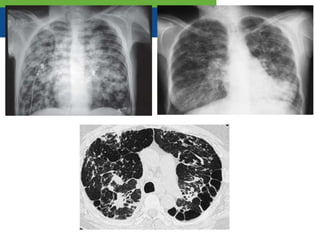

Radiografía de tórax

• Anteroposterior

• Lateral

Dos proyecciones

TAC-AR

Método de

elección para

• Bronquiectasias

Cilíndricas Varicosas Quísticas

Radiografía de tórax •Anteroposterior • Lateral Dos proyecciones

• 26.

TAC-AR Método de elección para •Bronquiectasias Cilíndricas Varicosas Quísticas